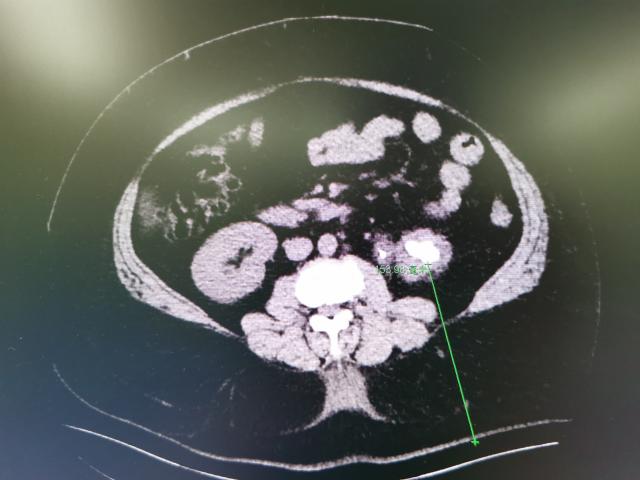

问题的关键主要有两点,其一是重度肥胖带来的超常规阻碍,其二是患者左肾结石的大小和位置。如果选择经尿道输尿管软镜处理结石,虽然身上不会有伤口,但因为患者结石的位置偏向于肾脏下部,软镜碎石存在一定困难,并且由于结石并不算小,输尿管软镜手术很可能无法一次完全清石。如果选择经皮肾镜手术,也就是在腰上面“打个洞”,虽然可以一次清石,但重度肥胖导致患者皮肤到肾脏的距离太长,常规的手术器械很可能无法满足手术要求。肖博与薛女士充分沟通后,薛女士明确提出了一次清石的诉求,综合考虑各方面因素,最终决定各位患者实施我院泌尿外科特色手术——超声引导下经皮肾镜手术。

但这场手术与以往大有不同,考虑到患者的特殊体型与麻醉问题,常规通过俯卧位进行的手术,这次需要改为侧卧位,穿刺点也由后腰相应改为侧腰。肥胖导致的超声影像不清晰、定位不够精准、手术习惯的变化、麻醉给药的用量与顺序等问题都给主刀医生和麻醉医生带来了挑战。5月底,在泌尿外科主任李建兴的亲自坐镇指挥下,我院泌尿外科团队为患者进行手术。侧卧位和肥胖都明显增加了超声引导下经皮肾镜手术的难度,肖博凭借丰富的手术经验,准确定位,精准穿刺,快速清石,最终完美清除左肾结石,同时保证了麻醉的安全与手术的成功,术后体表仅留一根肾造瘘管。